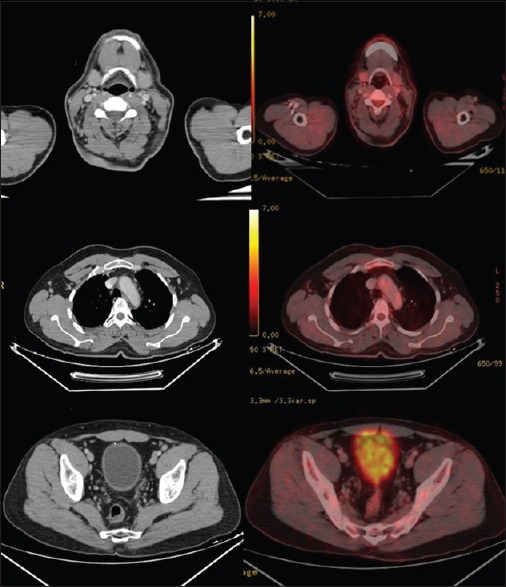

A 48-year-old male patient, normotensive, nondiabetic diagnosed with chronic lymphocytic leukemia (flow cytometry proven). He was planned for six cycles of rituximab, cyclophosphamide, doxorubicin, vincristine, and prednisolone. His pretreatment positron emission tomography-computed tomography (PET-CT) revealed multiple fluorodeoxyglucose (FDG) avid hypermetabolic lymph nodes in both supra- and infra-diaphragmatic regions [Figure 1].

| Figure 1:Positron emission tomography-computed tomography scan dated May 23, 2015 revealed multiple fluorodeoxyglucose avid hypermetabolic lymph nodes in both supra- and infra-diaphragmatic regions